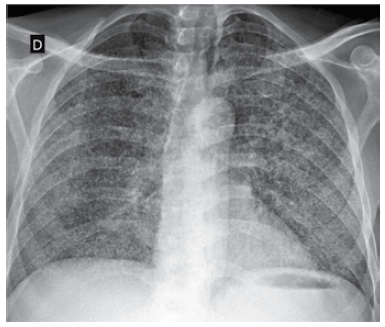

Paciente de 33 anos, HIV positivo, apresenta quadro de 1 mês com tosse seca, febre noturna, perda de peso, sudorese intensa, anorexia, adinamia e queda do estado geral. Ele não faz tratamento antirretroviral. Nega escarro hemoptoico e sintomas neurológicos ou gastrointestinais. Exame físico: consciente, orientado e anictérico; pressão arterial: 110 x 65 mmHg; pulso: 112 bpm; temperatura: 37,3 ºC; oximetria de pulso com saturação de 91%. A desidrogenase lática sérica é normal. A radiografia realizada é mostrada a seguir.

A principal hipótese diagnóstica é